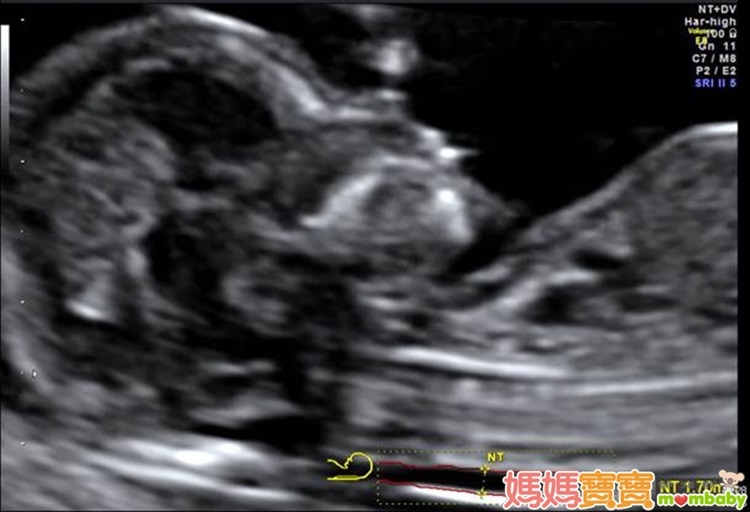

利用高解析度的超音波來檢查胎兒頸部透明帶厚度,以確認胎兒是否具備染色體或構造異常等疑慮,進而接受更進一步的評估,正是這個產檢項目的宗旨。頸部透明帶的測量部位,為胎兒頸椎表皮與表皮底下軟組織的間隙,之所以會發展這樣的篩檢方式,是因為藉由以往的臨床經驗中逐漸得知,染色體與器官構造異常的胎兒,頸部透明帶似乎皆有變厚的傾向,例如唐氏症、透纳氏症候群、先天性心臟病等,這些疾病往往合併胎兒膠原組織組成改變,或淋巴及心血管循環出現異常,進而導致頸部透明帶變得較厚;因此,醫界便開始利用這個現象來回推檢測,觀察頸部透明帶較厚的胎兒是否有較高機率發生異狀,才會演變為現今的胎兒頸部透明帶篩檢。

頸部透明帶的檢查週數為懷孕第11週~第13週又6天之間,有些準媽媽可能會以月經週期來推算懷孕週數,但如果忘了最後一次的月經日期或平常月經不規則的孕婦,醫師會利用超音波來測量胎兒的頭臀徑(頭到臀部的長度,也就是胎兒坐姿高度),若頭臀徑介於36~84公厘之間,也達到適合檢查頸部透明帶的標準。

不過,不建議僅依靠頸部透明帶的測量結果來做為染色體是否異常的依據,因為單看此篩檢結果,而未結合血清檢查,準確度只有六成左右,甚至會造成不必要的誤會。因此,現在婦產科醫學界認為,應將頸部透明帶檢查視為第一孕期唐氏症篩檢的一部分,其他相關檢查還包括抽血檢驗 β-hCG(人類絨毛膜性腺激素)與PAPP-A(妊娠相關血漿蛋白-A),同時配合孕婦的年齡、種族等條件,將這些數值綜合之後,用電腦軟體計算胎兒出現染色體異常的機率或高或低,才是最為恰當的篩檢方式。